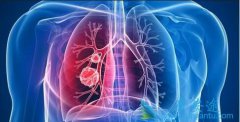

肺癌患者能活多久与规范的肺癌治疗有关

肺癌是一种高度恶性的肿瘤,在我国肺癌的发病率和死亡率都相当高。人们一旦确诊是肺癌以后,无论是对患者本身还是患者的家人带来巨大影响,对癌症的恐惧会使肺癌患者的整个家庭都笼罩在恐惧和死亡的阴霾中。很多肺癌患者或其家属都很关心,到底得了肺癌 ...

肺癌是目前各种肿瘤中发病率和死亡率最高的肿瘤,被称为肿瘤第一杀手。当肺癌发生骨转移,就意味着肺癌已发展到最晚的一期,治疗效果比较差,所以发现肺癌后,应接受专业医师指导,积极恰当地治疗,避免病情进一步发展。 肺癌骨转移症状 有哪些?疼痛是 ...